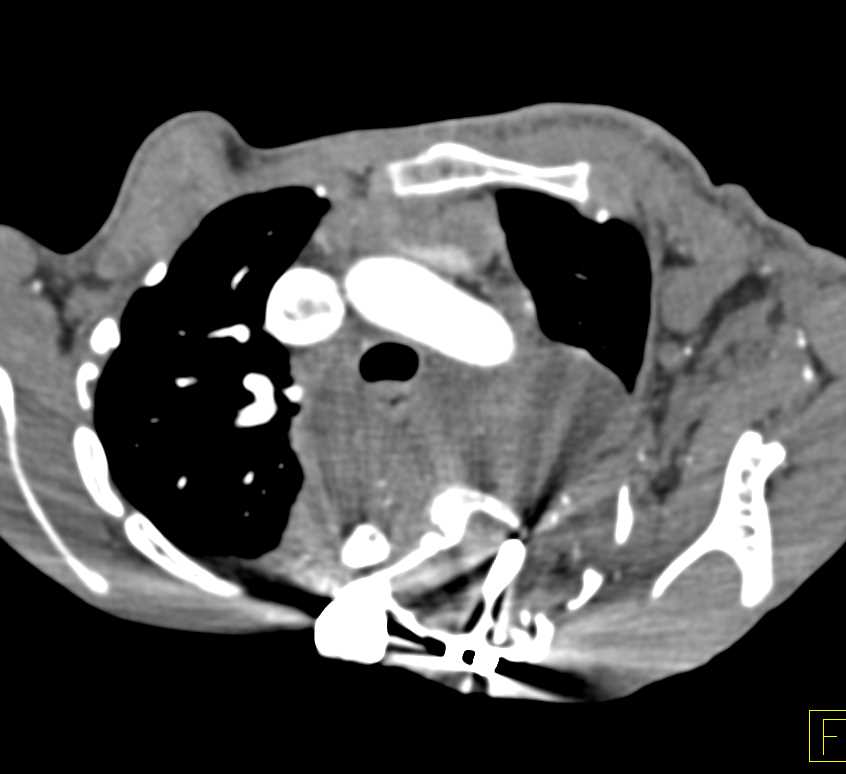

Extramedullary Hematopoiesis